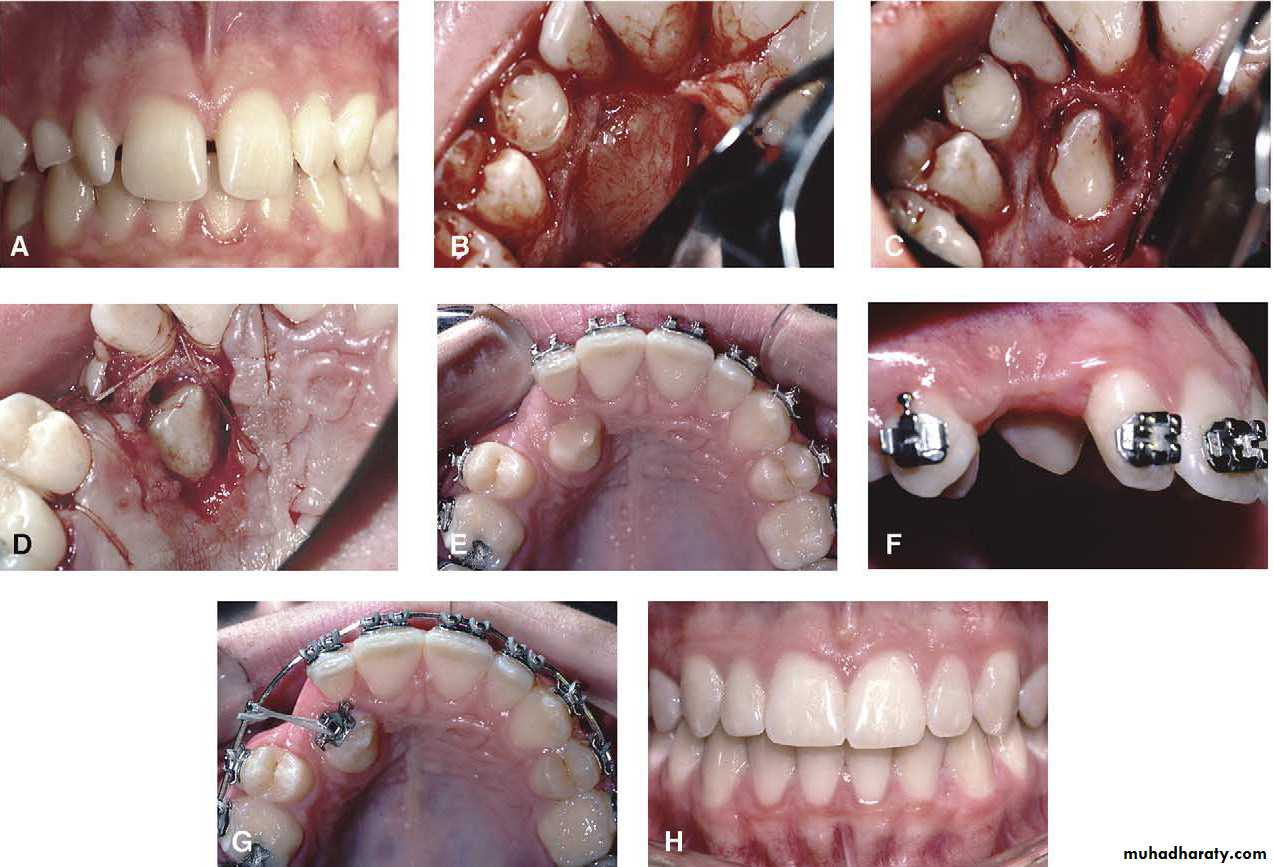

Transplantation and surgical repositioning

The success rate with transplantation is highest for1- unerupted teeth which have open apices because of the possibility of revascularization .

2- It is essential to establish that there is sufficient space to accommodate the canine crown. minimal space deficiency may be overcome by grinding of the crown , but otherwise orthodontic therapy may be required to move the premolar distally .

3-The canine should be extracted carefully and

transferred to the surgically prepared socket in the dental arch with the minimum of delay.It is preferable that the root surface should not be touched either with instruments or fingers as the viability of the cementum and periodontal membrane remnants will determine the success of the transplant. The tooth is stored under the flap to keep the tooth moist until the new socket is prepared .

Root filling is not attempted so as to reduce handling of the tooth .

4- The transplanted tooth should be splinted in its new position for a month after the operation .Surgical repositioning

In the technique of surgical repositioning , the displaced tooth is not extracted but rotated or tilted about its apex . It is indicated when the tooth is fully erupted , but the crown is out of the line of the arch .There must be adequate space for the canine in its correct position